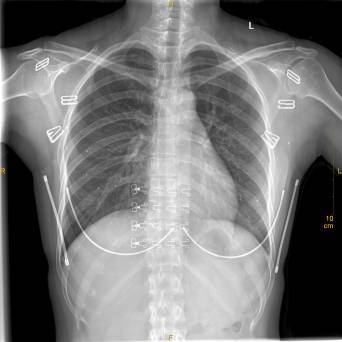

②这个好像简单一点。

X光拍片为什么要等【影像科普】拍片为什么会要求脱衣服?_https://www.jmylbn.com_新闻资讯_第5张